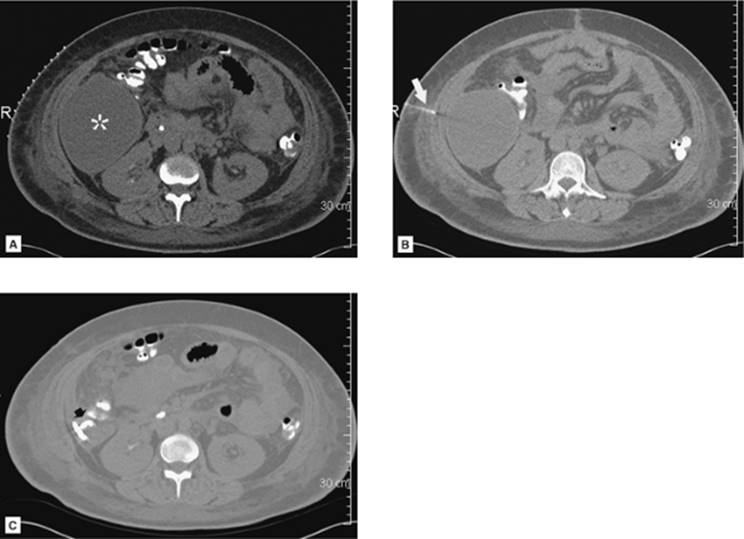

000204

Figure 35.4. CT-guided drainage of infrahepatic abscess. A: CT scan through the fluid collection (asterisk) with localizer grid applied on the skin over the target. B: Following determination of pathway, entry site marking, sterile skin prep and drape, and local anesthesia the access needle is advanced under CT guidance into the fluid collection. Repeat CT is performed to evaluate needle path and depth (arrow). C: Postdrainage obtained at the same level as A shows loop of drainage catheter (short arrow) in markedly decompressed abscess cavity. (Case courtesy of Lauren Alexander, MD, Gainesville, FL.)

000159

Figure 35.5. A 19-year-old patient with sepsis and cough. A: Axial CT at the level of the midchest demonstrates an 8.5-cm fluid collection in the right posterior hemithorax (asterisk) with compression atelectasis of the adjacent lung. Direct percutaneous access is blocked due to inferior margin of the scapula, overlying ribs, and aerated lung. B: Patient was placed in a left-side-down decubitus position. Change in position provides direct posterior access to the fluid collection. A localizer grid has been placed to mark site of access. C: Access gained with micropuncture needle system and then a 14 Fr drain placed over a wire. Fluid aspirated with syringe and then drain was secured in place and connected to suction bulb. D: Postdrain placement CT. (Case courtesy of Lauren Alexander, MD, Gainesville, FL.)